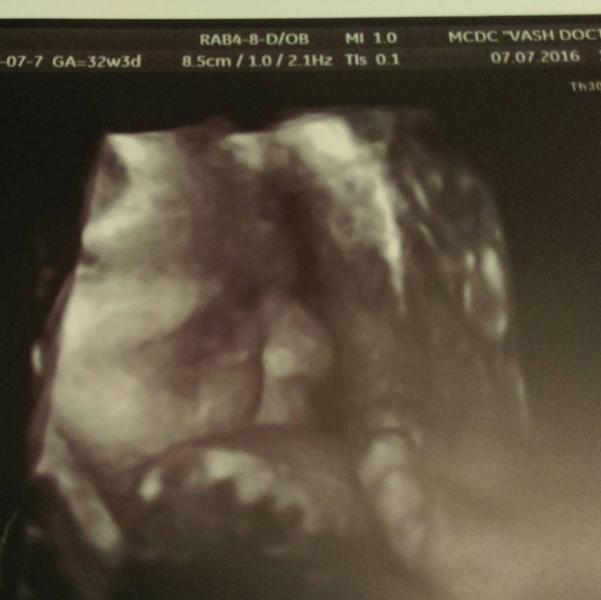

@svetlanamalina, а, у Русиновой, ясно))) что в Вашем докторе, это я увидела 😄 славный малыш 😊👍🏼

@kristi2202 мы очень компактные)) на 30, 3 были 1506 гр., а вот на 32,3 поставили 1635 гр.